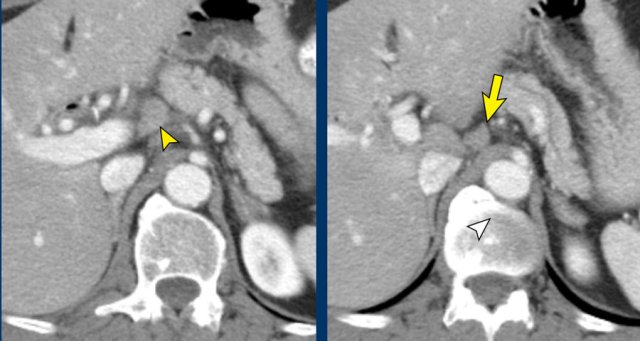

Vessel irregularity

Axial CT shows:

- Tumor in the body of the pancreas (white arrowhead).

- Focal < 90º contact with the SMA.

- More extensive 90º – 180º contact with the SMV , which is slightly narrowed and deformed (yellow arrow).

- Dilatation of the pancreatic duct

The coronal reconstruction shows:

- Vessel wall irregularity of the SMV is better appreciated on this coronal reformat (arrow).

- Thrombosis in SMV side branches (small green arrows).